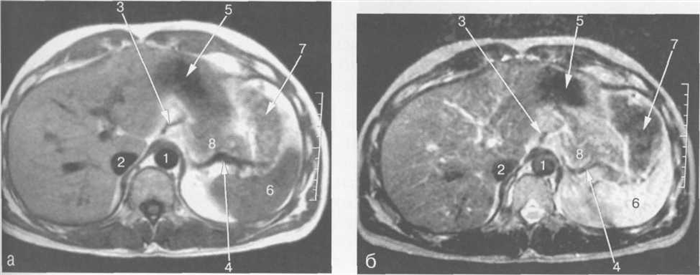

Рис. 11.9. МРТ брюшной полости в аксиальной плоскости на уровне печеночных вен.

1 — аорта; 2 — пищевод; 3 — непарная вена; 4 — полунепарная вена; 5 — спинной мозг; 6 — нижняя доля правого легкого; 7 — нижняя полая вена; 8 — правая печеночная вена; 9 — средняя печеночная вена; 10 — левая печеночная вена; 11 — левый желудочек сердца; 12 — ветви правой воротной вены; 13 — селезенка.

Рис. 11.10. МРТ брюшной полости в аксиальной плоскости на уровне пищеводно-желудочного перехода.

1 — аорта; 2 — пищеводно-желудочный переход; 3 — непарная вена; 4 — полунепарная вена; 5 — ножка диафрагмы; 6 — нижняя доля правого легкого; 7 — нижняя полая вена; 8 — правая печеночная вена; 9 -средняя печеночная вена; 10 — желудок; 11 — селезенка.